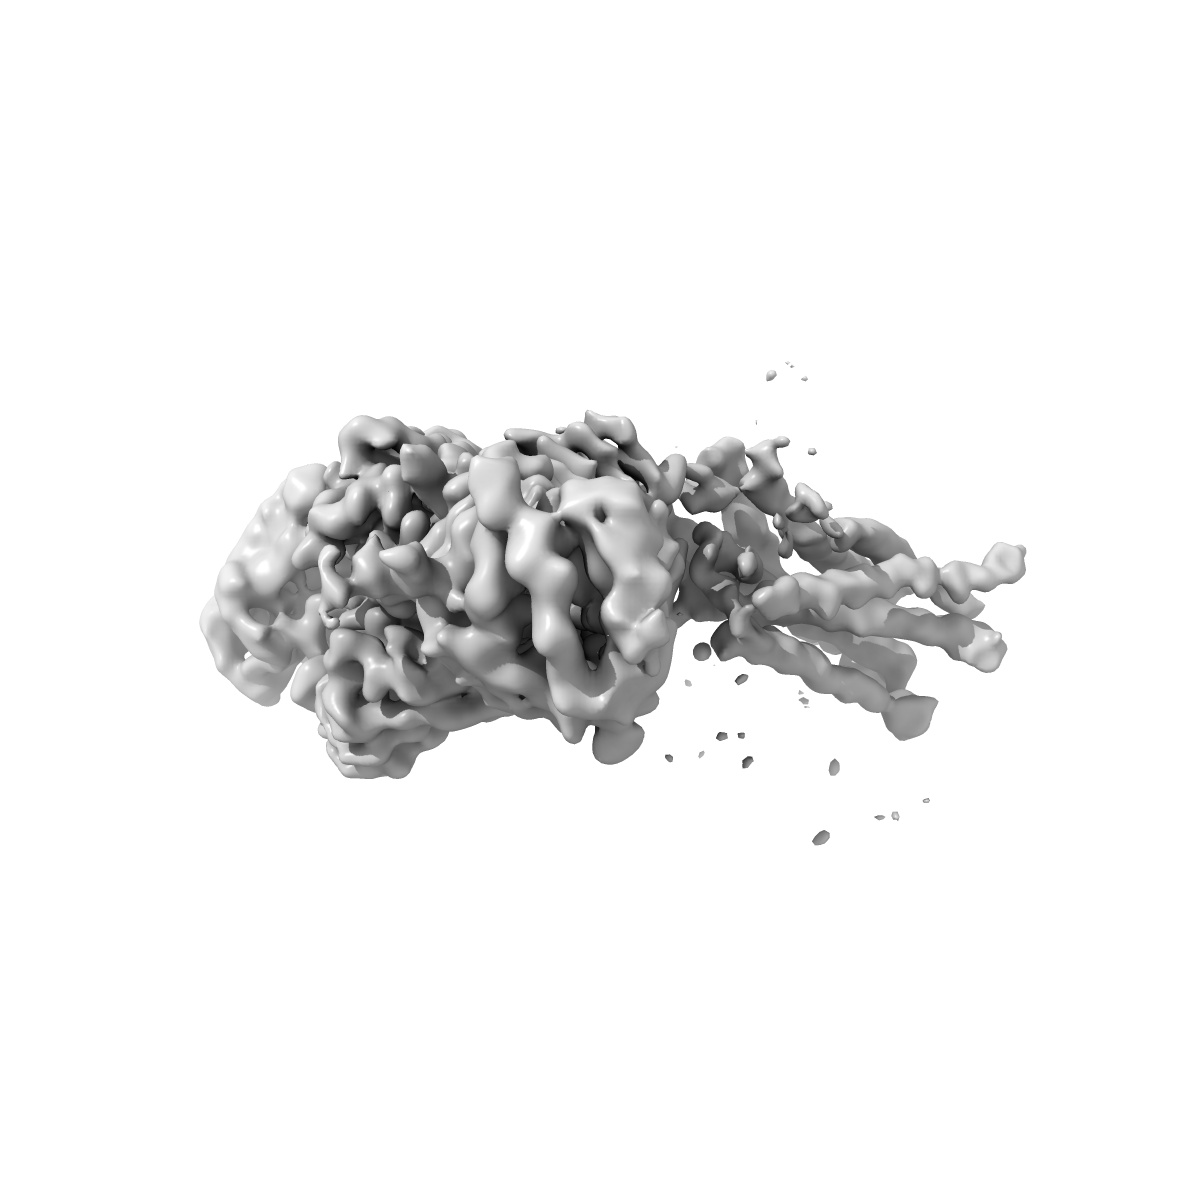

Human Thyrotropin receptor bound by CS-17 Inverse Agonist Fab/Org 274179-0 Antagonist

Single-particle3.1 Å

Sample: Human Thyrotropin receptor in complex with the murine inverse agonist Fab fragment CS-17